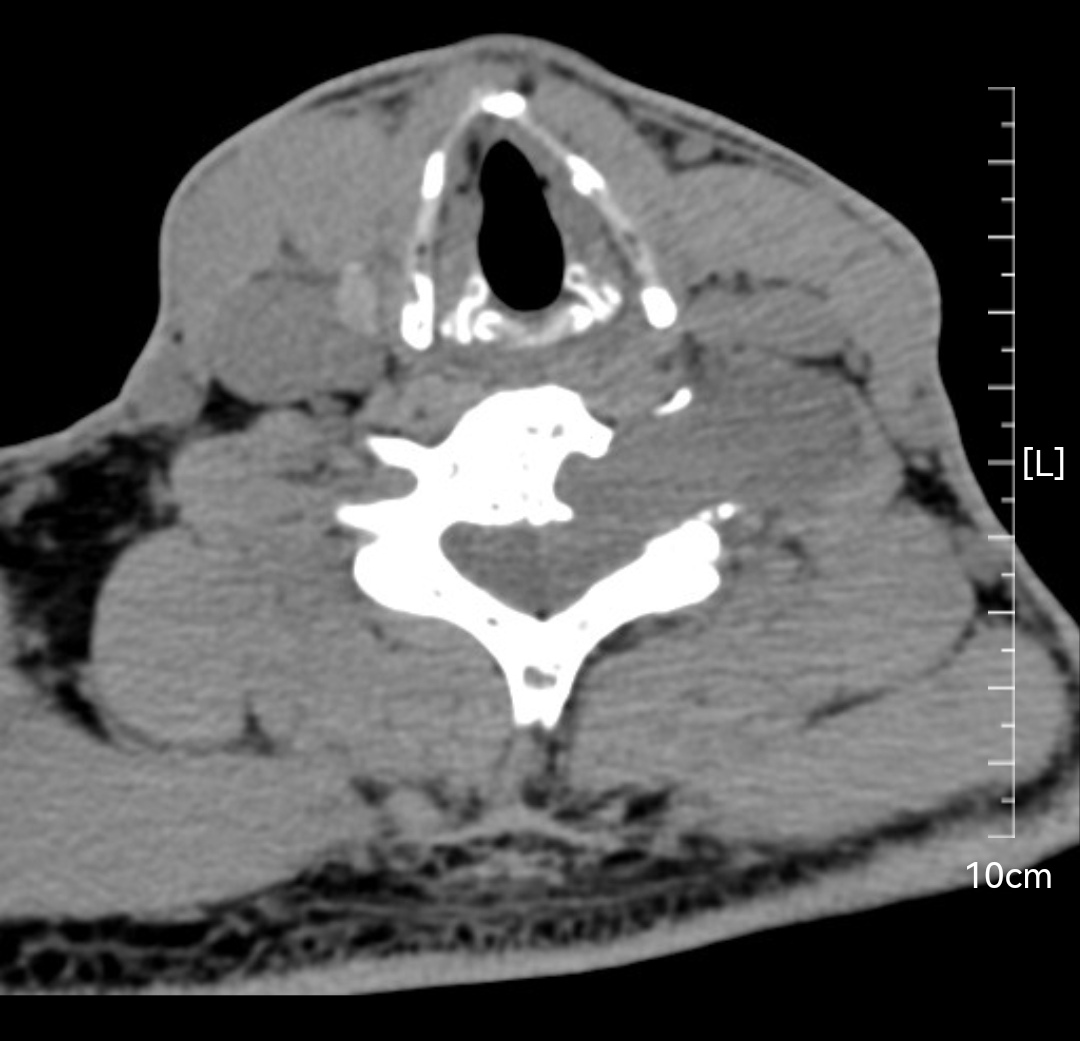

颈椎哑铃型神经纤维瘤,椎间孔汇合,安全又便于操作~